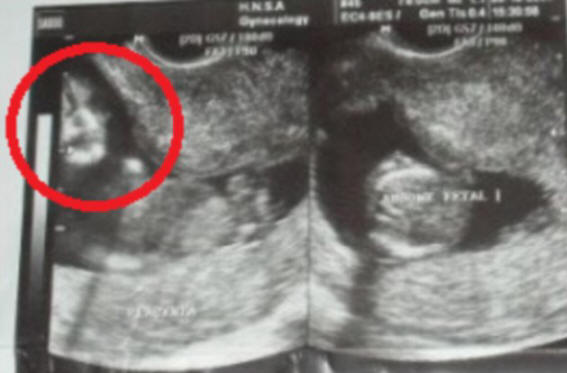

Aviopuoliso (t) Marcelo ja Famela de Souza (Marcelo ja Phamela de Souza) oli järkyttynyt nähdessään syntymättömänsä lapsen ultraäänellä kuva samanlainen kuin myöhään äiti Marcelo.

Yhdessä kuvassa ilmestyi outo “kasvot” yhtäkkiä jostain kohdusta

Menettely suoritettiin 10 raskausviikolla ja tulevalla isällä huomasi heti näytöllä omituisen kuvan, mutta pelkäsi sanoa tästä vaimolleen. Hän kuitenkin itse näki kasvot kuvassa ja näytti sen miehelleen. Marcelon mukaan se oli hyvin samanlainen kuin äitinsä, joka kuoli vain 4 kuukautta ennen.

Itse lapsen kuvassa ei ollut mitään epätavallista